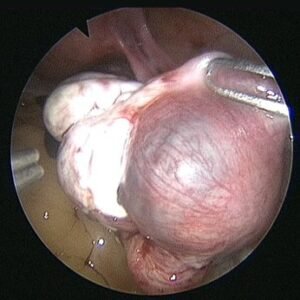

The diagnosis is also confirmed with ultrasound and blood flow studies (Doppler) during which the sac may be visualized in the region of the adnexa close to ovary. The treatment may be medical with methotrexate (chemotherapeutic agent) given either as oral medication or an injectable, depending on the combined laboratory and clinical findings. If surgical intervention is decided upon then laparoscopic surgery will be performed in most patients who are hemodynamically stable. In cases where the patient presents late with the symptoms or the pregnancy has ruptured with bleeding into the abdomen laparotomy (10%) is performed.

The affected tube is most often if not always removed after examining the opposite tube and assessing the patient’s chances of future conception. Even with one healthy tube it is possible to conceive. In our experience removal of tube almost always reduced chances of recurrence and helped improve pregnancy rates by either trying for conception with the opposite tube or with ART.